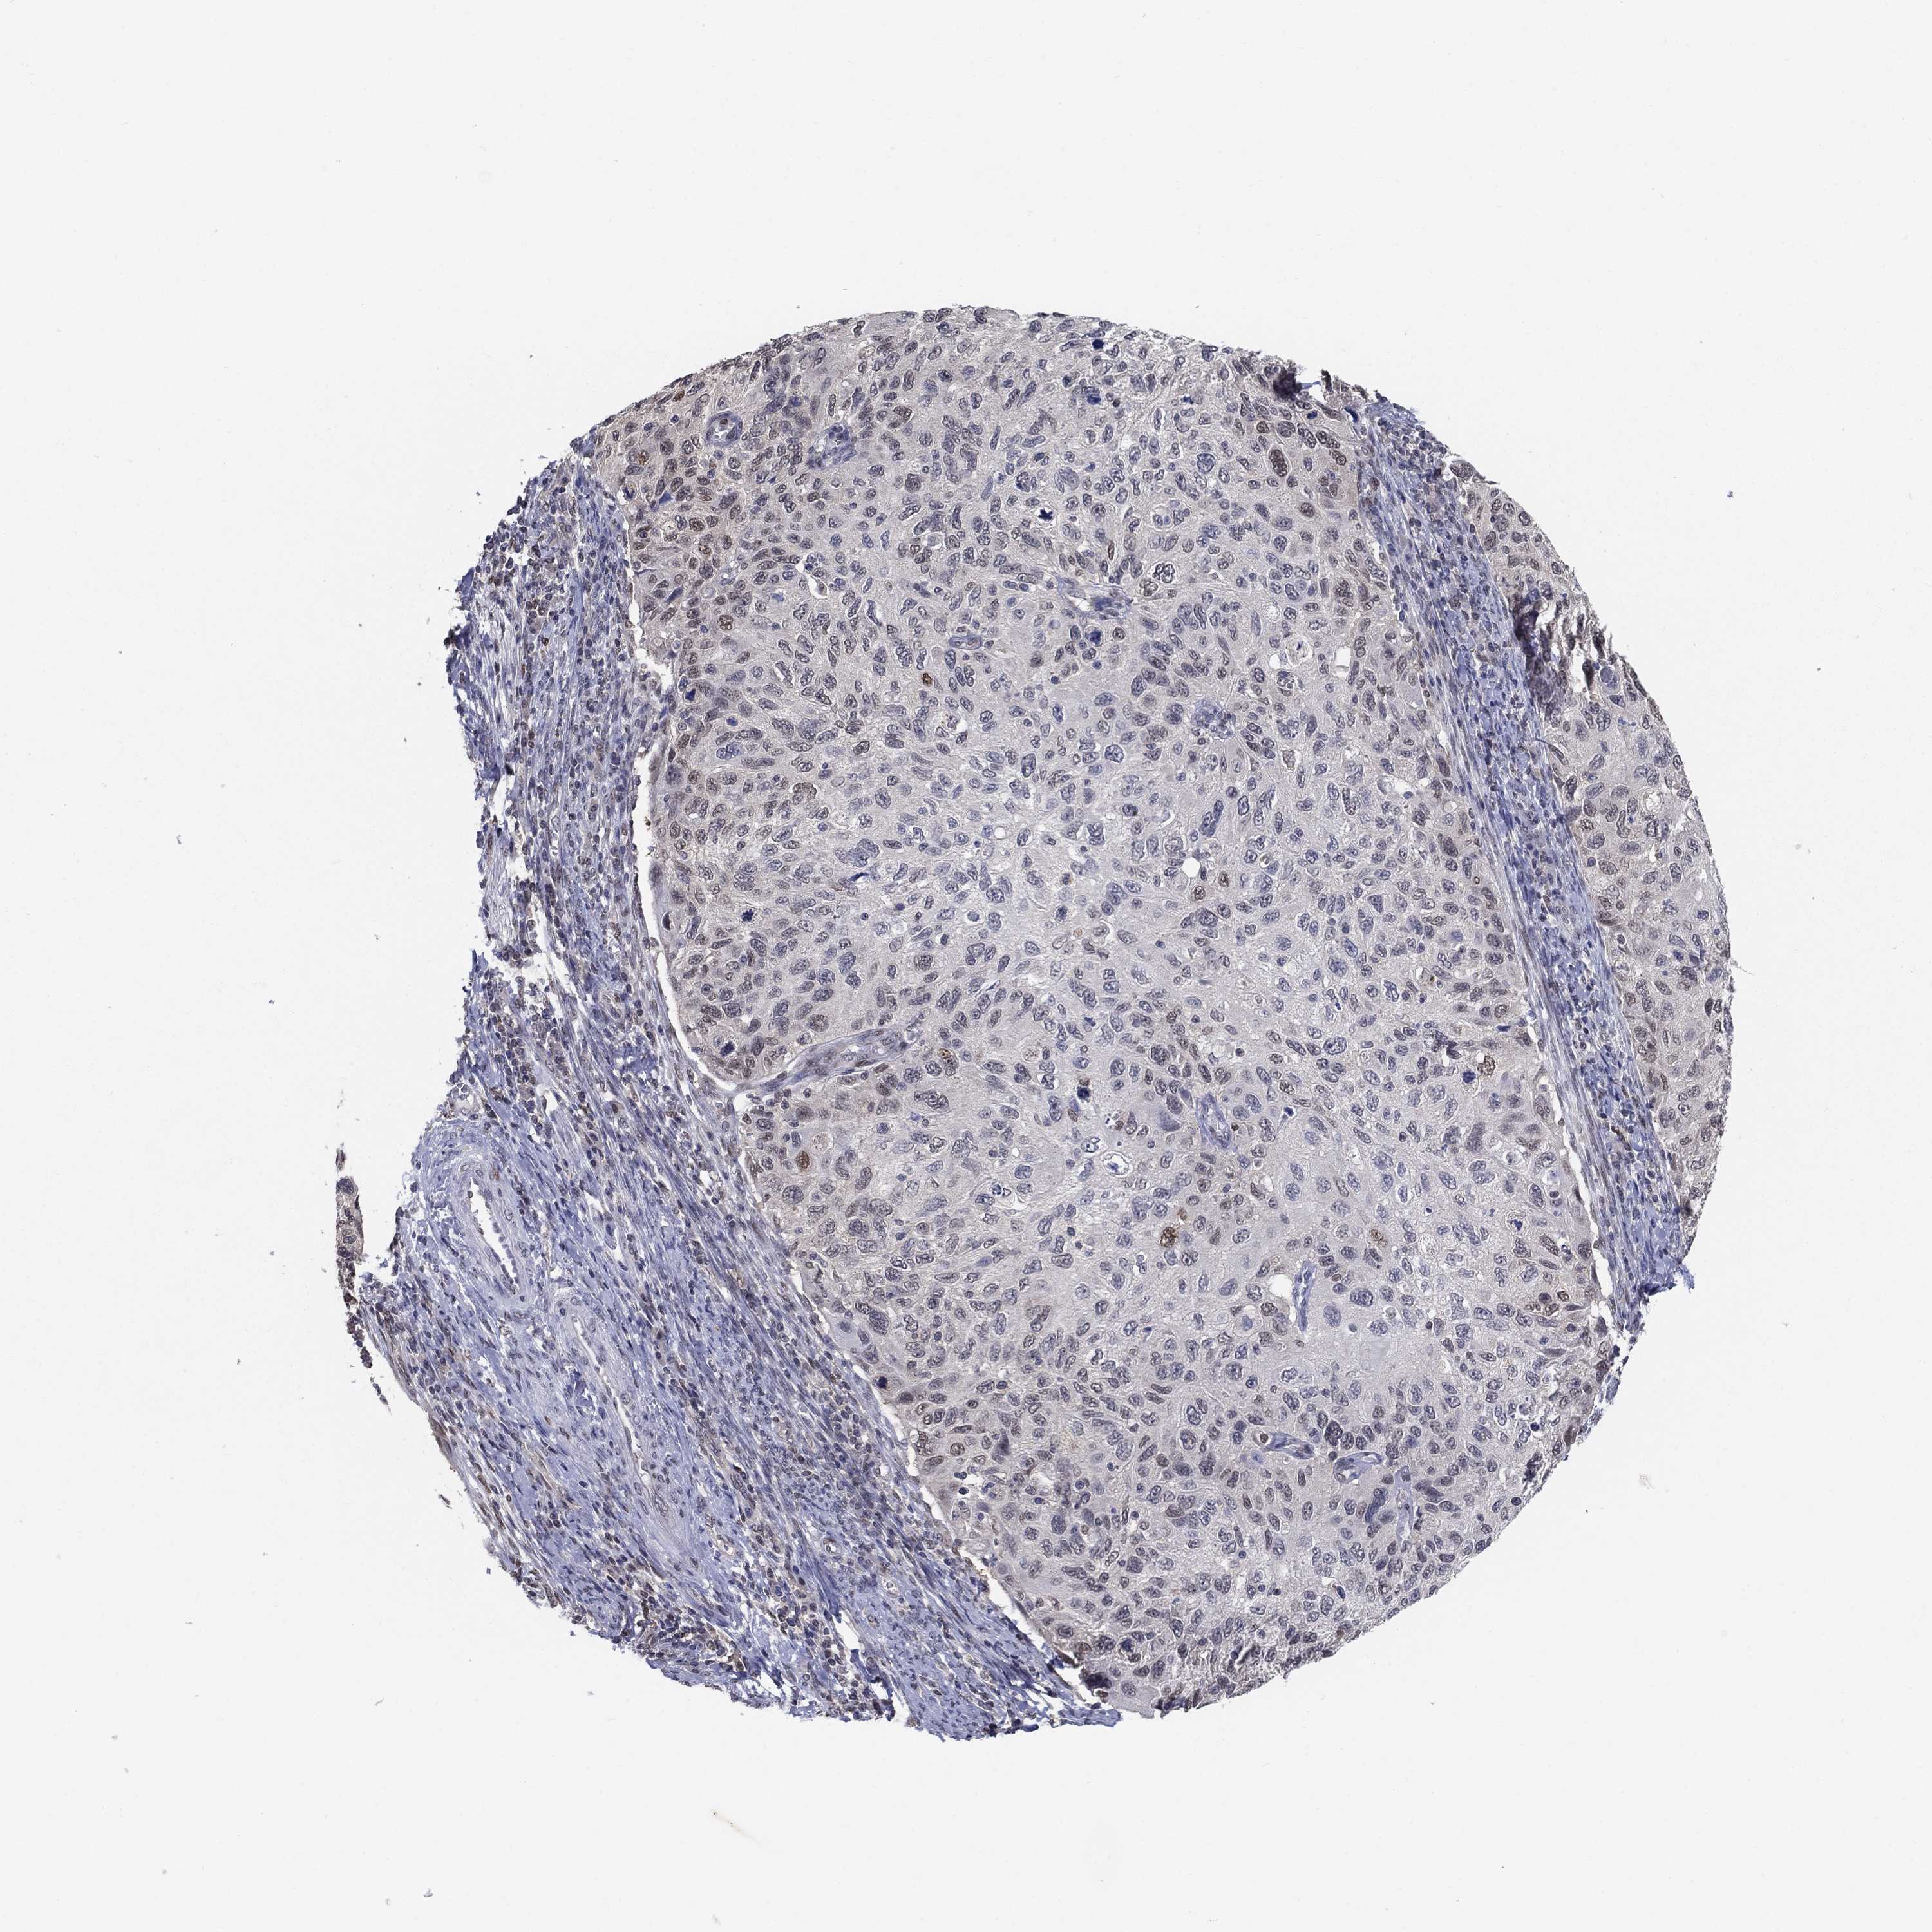

CERVICAL CANCER - Protein expressioni

A mouse-over function shows sample information and annotation data. Click on an image to view it in a full screen mode. Samples can be filtered based on level of antibody staining by selecting one or several of the following categories: high, medium, low and not detected. The assay and annotation is described here.

Note that samples used for immunohistochemistry by the Human Protein Atlas do not correspond to samples in the TCGA dataset.

Antibody stainingi

Antibody staining in the annotated cell types in the current human tissue is reported as not detected, low, medium, or high, based on conventional immunohistochemistry profiling in selected tissues. This score is based on the combination of the staining intensity and fraction of stained cells.

Each image is clickable and will lead to virtual microscopy that enables deeper exploration of all samples and also displays staining intensity scores, fraction scores and subcellular localization as well as patient and tissue information for each sample.

Antibody HPA042294

Staining

High

Medium

Low

Not detected

Intensity

Strong

Moderate

Weak

Negative

Quantity

>75%

75%-25%

<25%

None

Location

Nuclear

Cytoplasmic/membranous

Cytoplasmic/membranous,nuclear

Squamous cell carcinoma, NOS

Adenocarcinoma, NOS